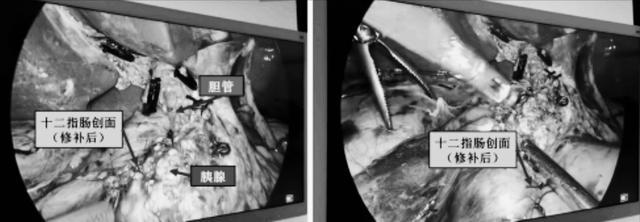

历经4小时,孙吉春教授团队切除部分胰腺,成功实现了病变的完整切除,同期切除胆囊(胆囊多发结石),未损伤胆管和胰管等重要结构。

对十二指肠残壁进行精细修补后,王晓艳教授、肖志明教授为患者行胃镜下胃空肠三腔营养管置入,为患者术后恢复及减少并发症风险保驾护航。术中快速病理提示梭形细胞瘤,与MDT团队术前间质瘤的判断亦相吻合。